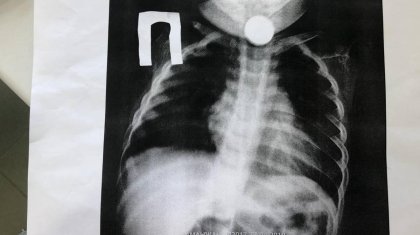

Ақтауда бір жарым жасар сәбидің өңешінен 10 теңгелік монета шықты

Ақтауда дәрігерлер «Фолея Катетерін» қолдана отырып, бір жарым жастағы баланың өңешінен бөгде затты алып шықты. Бұл туралы Маңғыстау облысты